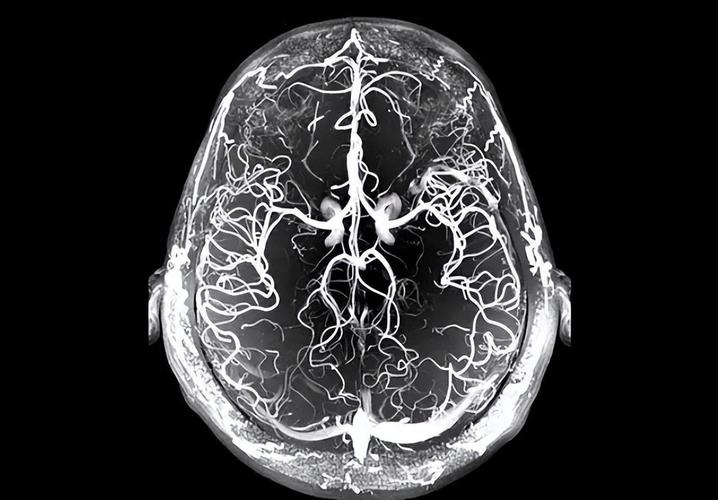

- MR Angiography (MRA): 评估 血管闭塞情况。

(图片来源网络,侵删)- MRA: 快速识别大血管闭塞(如颈内动脉、大脑中动脉M1段)。